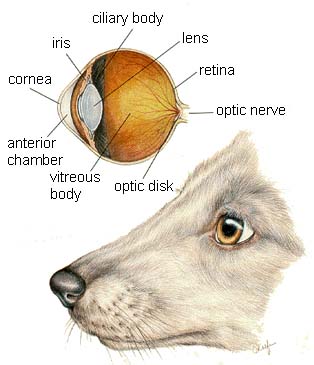

The organs of special senses allow the animal to interact with its environment; sight, taste, smell and hearing.

Dog Eyes